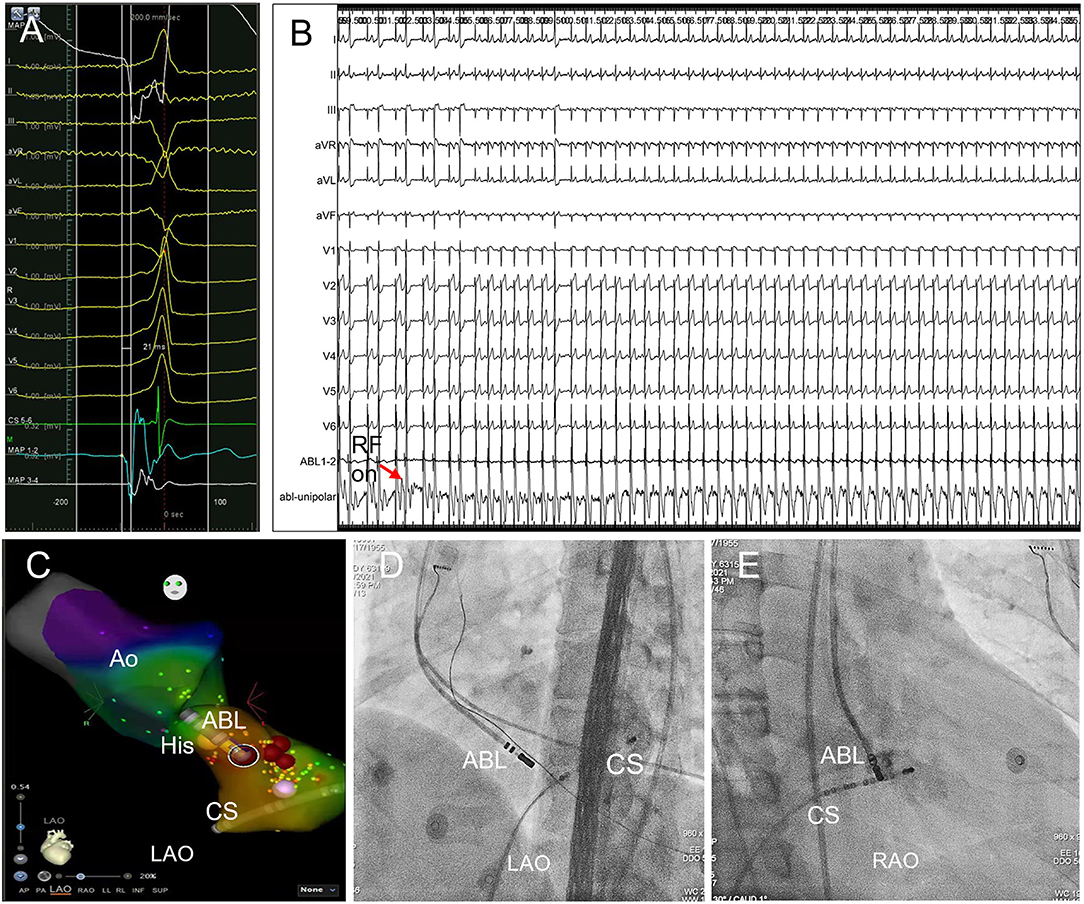

Figure 3. Trans-aortic retrograde ablation of left PHVA. (A) Tracings were unipolar MAP1, twelve-lead surface ECG, CS5−6, bipolar MAP1−2, MAP3−4. The local bipolar electrogram at the ablation target preceded the QRS onset by 21 ms with a sharp “QS” unipolar electrogram. (B) RF ablation 30W, 60s at the sub-aortic ablation target successfully eliminated the left PHVA without causing PR prolongation or AVB. (C) Activation mapping of the left PHVA region and the aortic root. The catheter tip was positioned at the ablation target ≈3 mm below the HB in the left ventricle. Ablation attempt (30W, 10 s) was not effective at other sites slightly away from the ablation target. Red dots represented ablation lesions. (D,E) The catheter placement at the left parahisian region on LAO and RAO fluoroscopic projection. Ao, the aorta; HB, the His bundle; CS, coronary sinus; ABL, the ablation catheter; RAO, right anterior oblique; LAO, left anterior oblique.

Left PHVA Ablation

Sub-aortic valve ablation was successful in all seven patients with left PHVA. In each of 4 patients with failed right parahisian ablation, the V-QRS time at the left-sided target was greater than that at the right-sided target (27 vs. 24, 31 vs. 29, 16 vs. 14, 33 vs. 31 ms, respectively). Compared with right PHVA, left PHVA exhibited higher proportion of precordial transition ≤lead V2 and lower proportion of QS shape in lead V1 on ECG recordings (Table 2). The procedural parameters were comparable except that the target-HB distance was greater in left sided group than that in right-sided group.